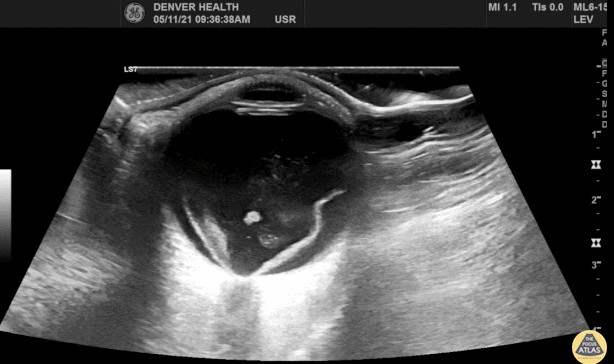

Finding on abdominal ultrasound exam.

What is a molar pregnancy?